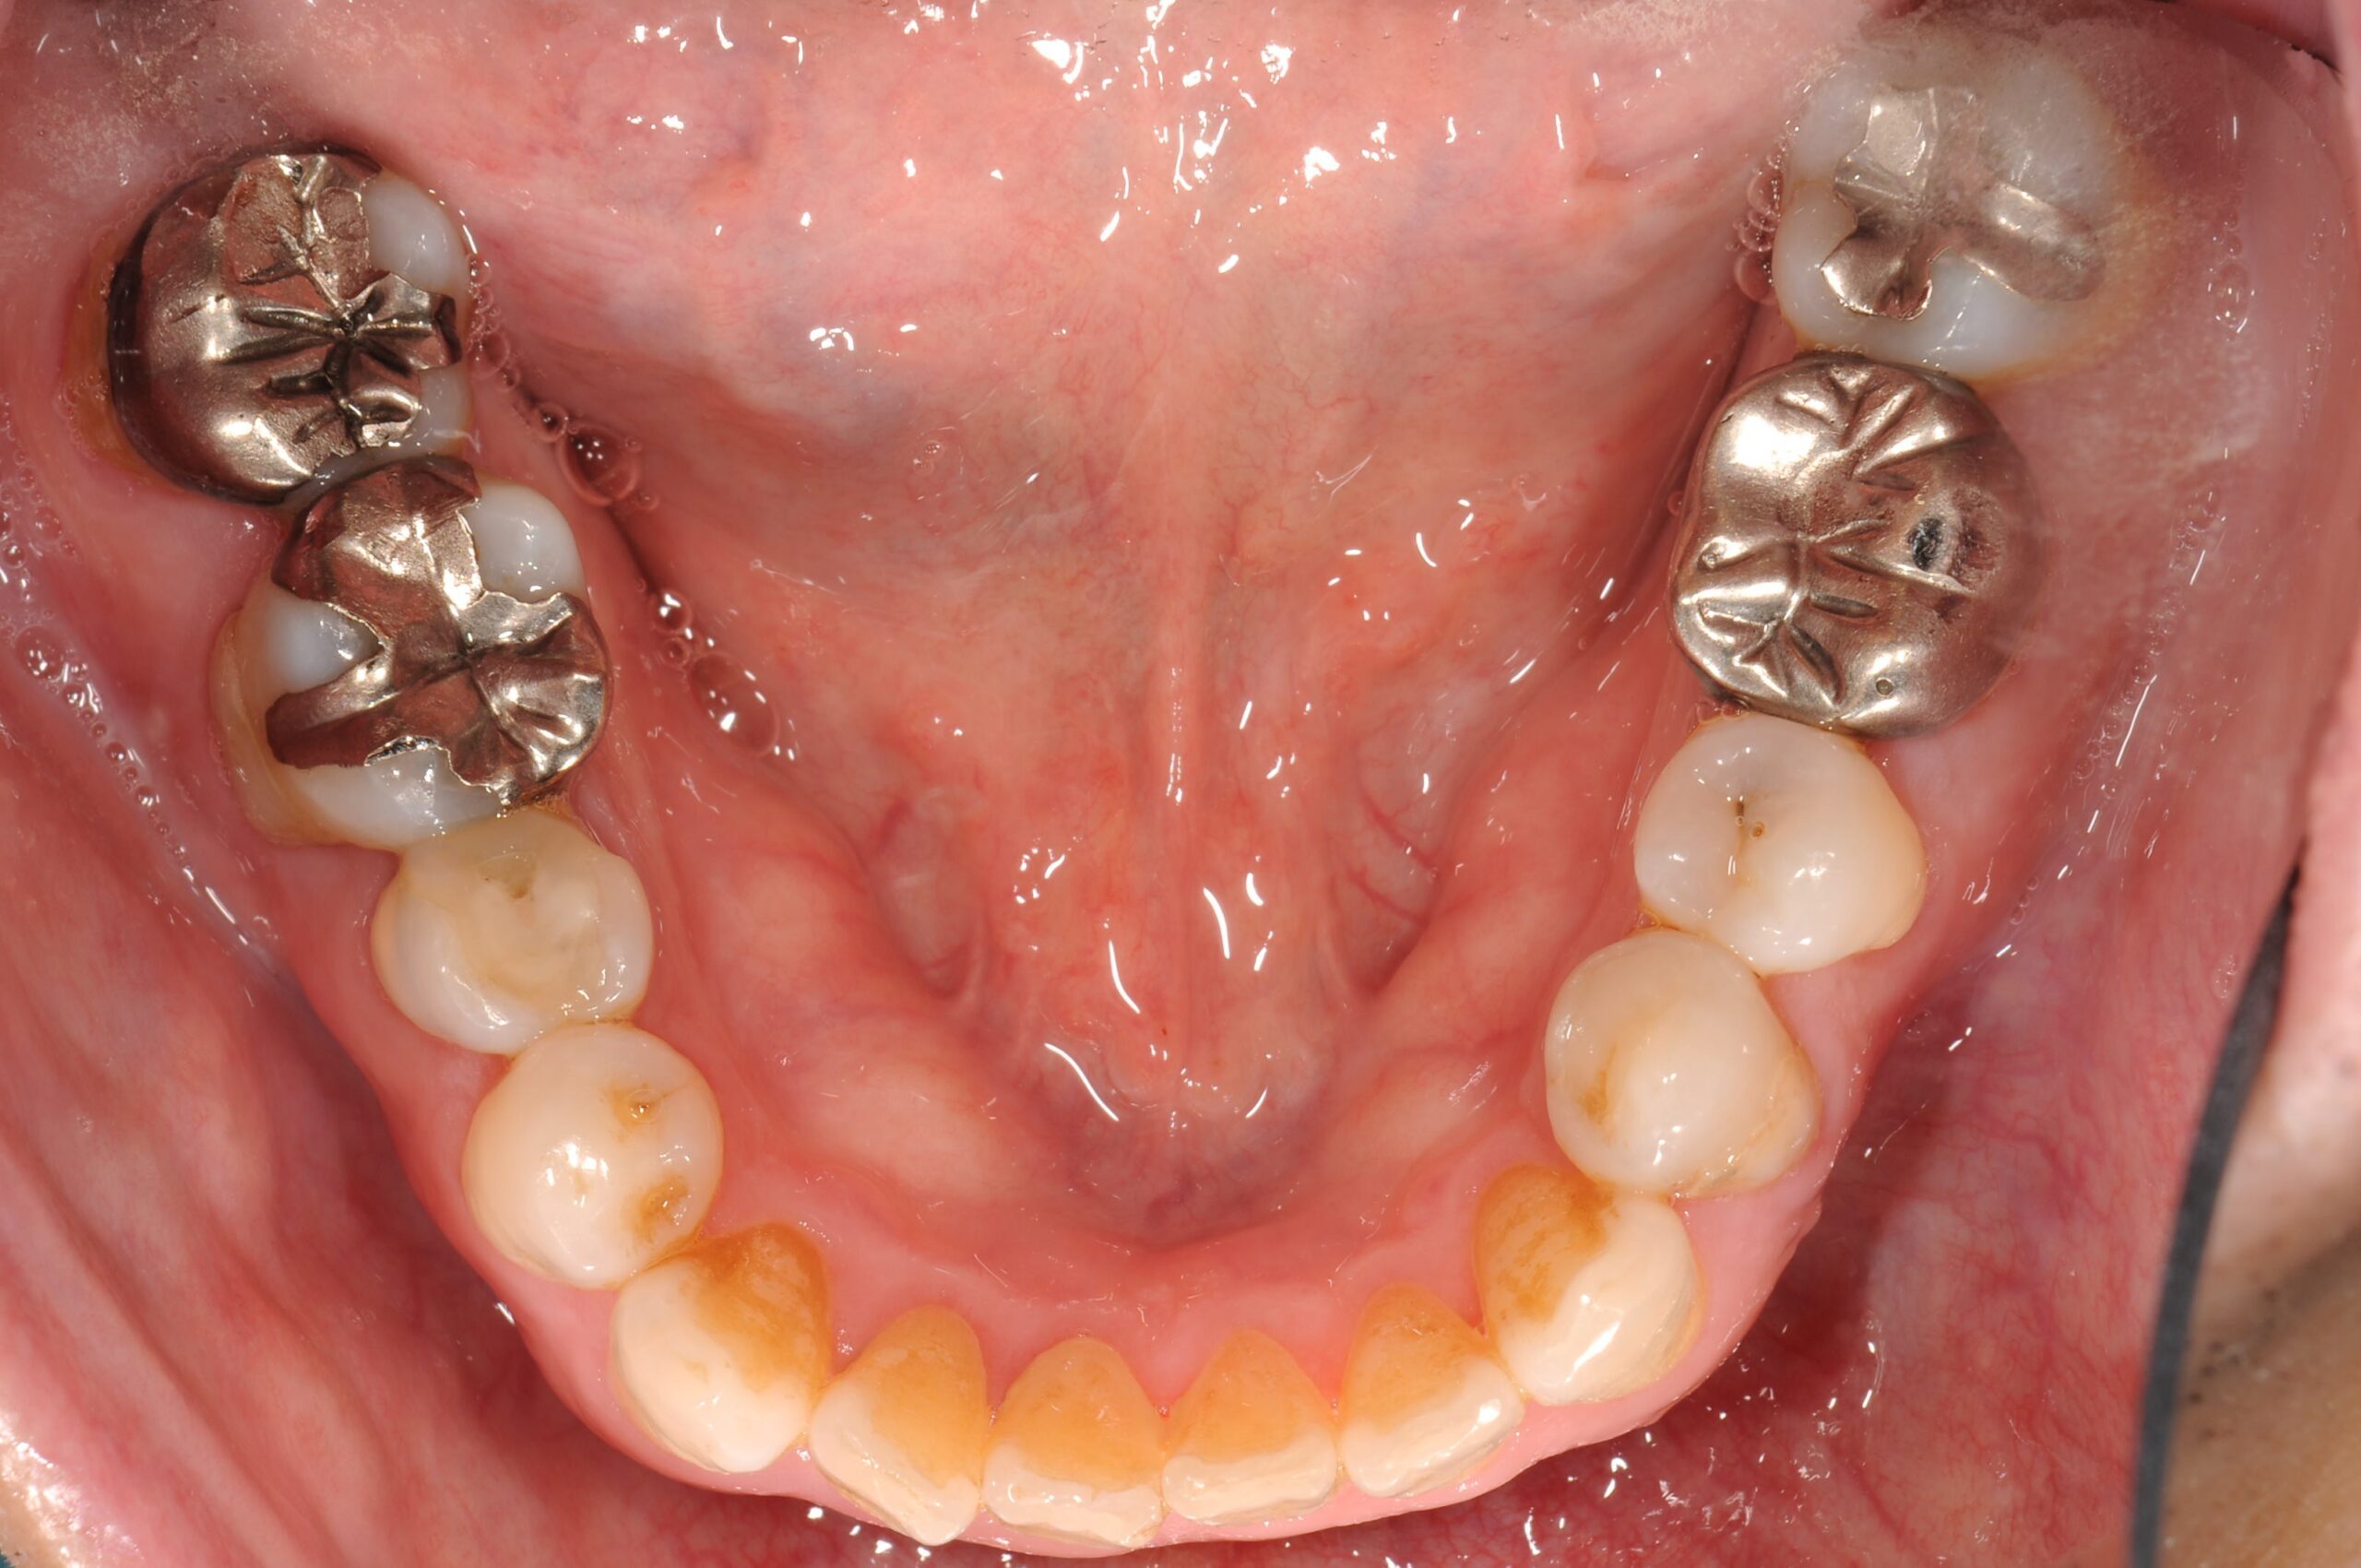

症例写真 after